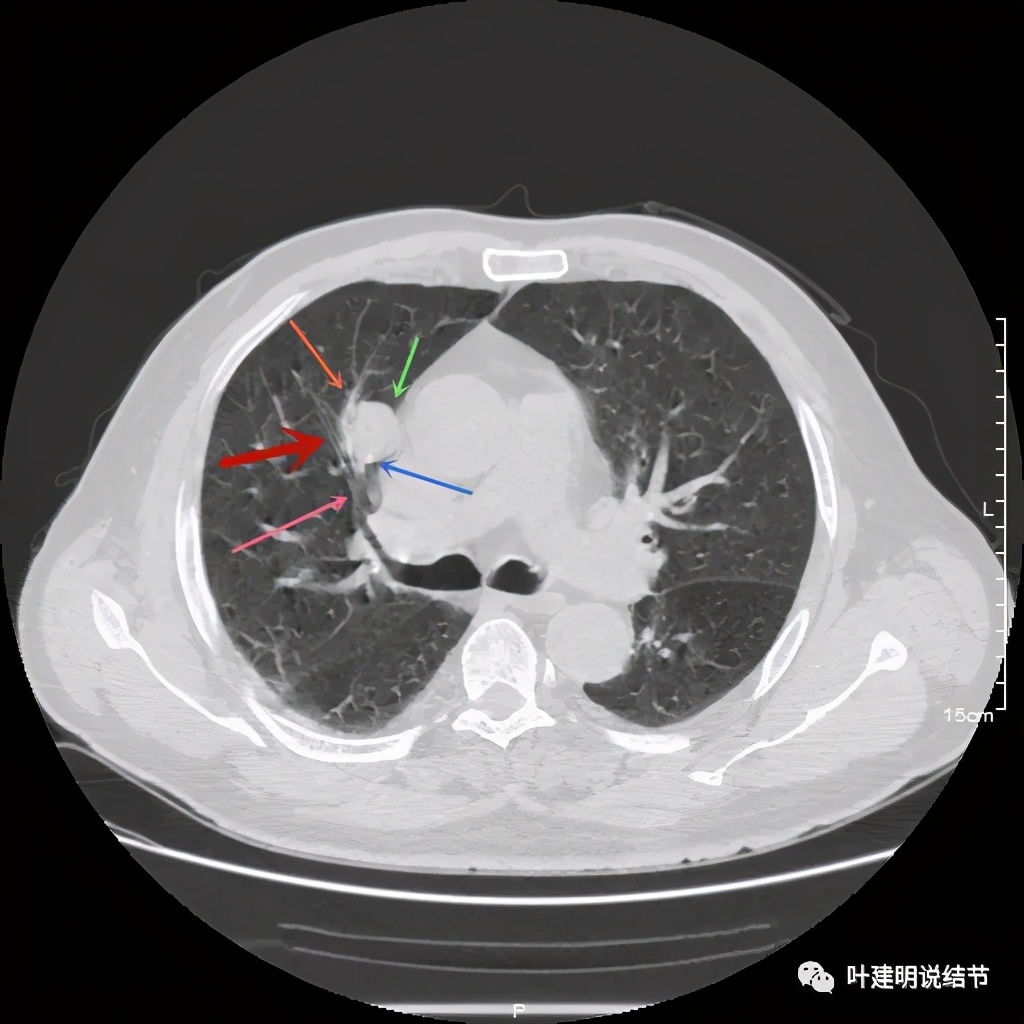

可见右上叶占位,我们现在知道了结果以后回头看,发现病灶的边缘在各个层面都是过于光滑(绿色箭头所示)。血管紧贴病灶边走行(桔色箭头所指),是不是有侵犯看不清楚,若是靶扫描加重建可能会更清楚点。支气管感觉也是贴着病灶走,但有的层面是不是截断,也不看的不太清楚。有的层面见局部有点状高密度(蓝色箭头所指),是不是错构瘤的局部钙化呢?若是纵隔窗又是如何?

上图示病灶

上图示病灶密度不均

上图示病灶局部点状高密度(蓝色);边缘过于光滑(绿色)

上图示病灶密度不均,但边缘过于光滑(绿色);支气管似有截断(粉色);局部有点状钙化(蓝色)